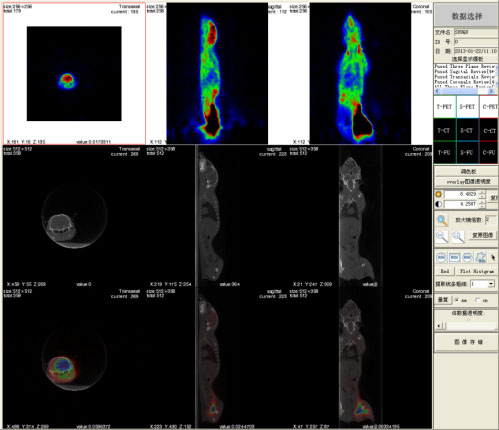

高能所自2005年成功研制出我国第一台高分辨小型PET扫描仪并面向社会推广应用以来,为全国各地的多家医院、高校、科研院所提供了生物医学领域多项科研课题的实验平台。其中昆明动物研究所在该平台上连续开展了多组有重要研究意义的实验,如动物脑抑郁模型及抑郁病形成机制研究。小型PET/CT扫描仪是昆明动物研究所在第一台小型PET成像平台上完成多组成像实验之后,向高能所订购的一台动物实验用双模态成像系统,系统具备PET、μCT(显微CT)及两者的融合成像功能。此外,该系统在技术上不仅为用户提供了传统的数据校正技术和准三维图像重建技术,还实现并提供了基于CT图像分割与连续一致特性的PET衰减校正技术、基于GPU加速的三维图像重建技术,实现并具备精确的PET与CT图像配准与融合技术。此次设备移机昆明,运输距离远,且进入云南后山路崎岖,颠簸严重,但设备经受住了考验,关键部件及与机架等到达后,安装工作进展顺利,且一次全面调试成功,进一步证明了我所在设备研制方面的技术水平与工程化能力。

在1月22日的验收会现场,专家组对系统软硬件各项指标进行了认真的评审,现场核查了设备的运行情况,审核了相关的文件档案,并对现场的动物实验结果表示满意。一致认为高能所圆满完成了研制工作,设备运行正常,可实现对大鼠、树鼩、猴子等动物的高精度扫描、重建与图像处理,各项技术指标达到或优于合同规定的要求,达到国际同类设备的先进水平,同意通过验收。同时,专家组也建议进一步支持该项目的后续研究和技术发展,加强用户与研制单位的进一步交流与合作,发挥分子影像技术在我国动物学研究领域的应用价值,推动相关科学研究领域的发展。

现场树鼩实验结果